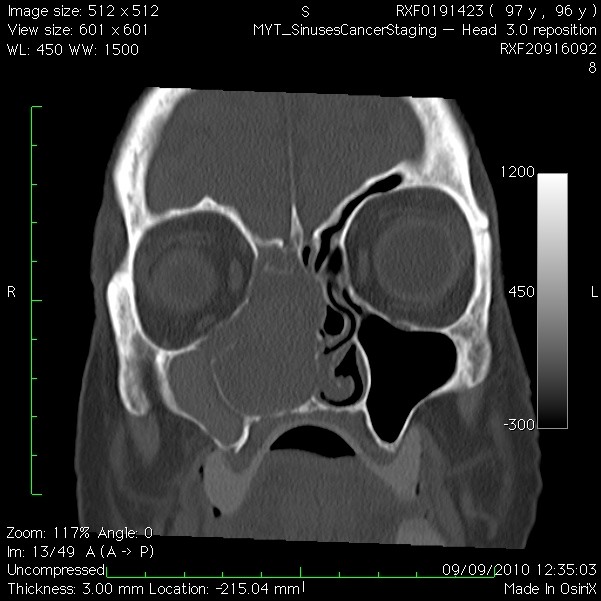

My right nostril is blocked for the last 10 years

My right nostril is completely blocked